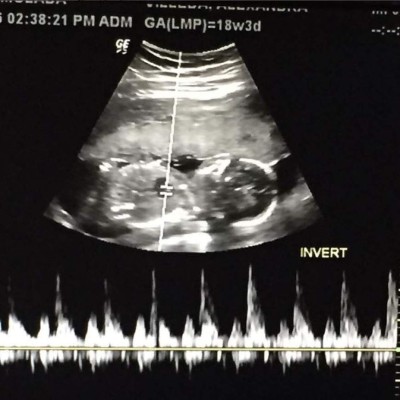

Ferrari publicó que será madre de un varón al que llamará Eduardo, así como el padre.

“Mi Principe. Muero por tenerte entre mis brazos y nunca soltarte!! #18semanas y #3dias”, escribió la artista acompañándolo con la imagen de su ultrasonido.